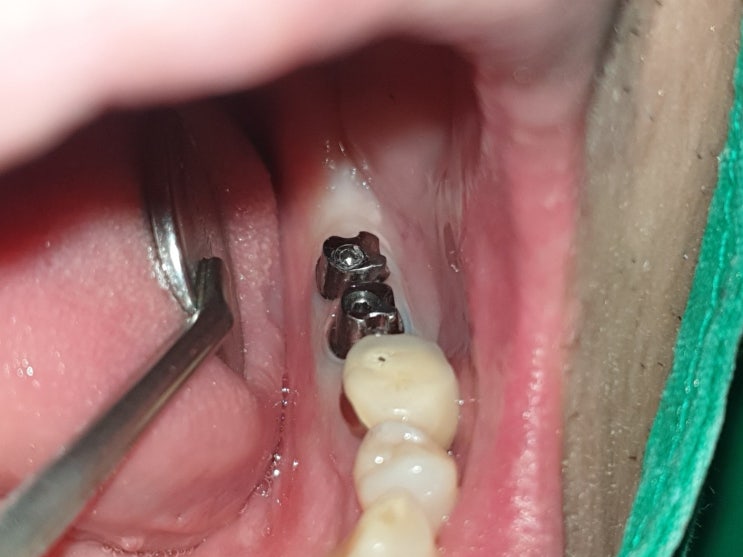

사랑니 자가치아이식 시술 12년 경과 모습 및 상악 완전매복 사랑니 수술발치 후 하악대구치에 자가치아이식

12년전 저에게 사랑니 자가치아이식 시술을 받고 한참을 내원 안하다가 왼쪽 아래 제1대구치의 발치진단을 ...